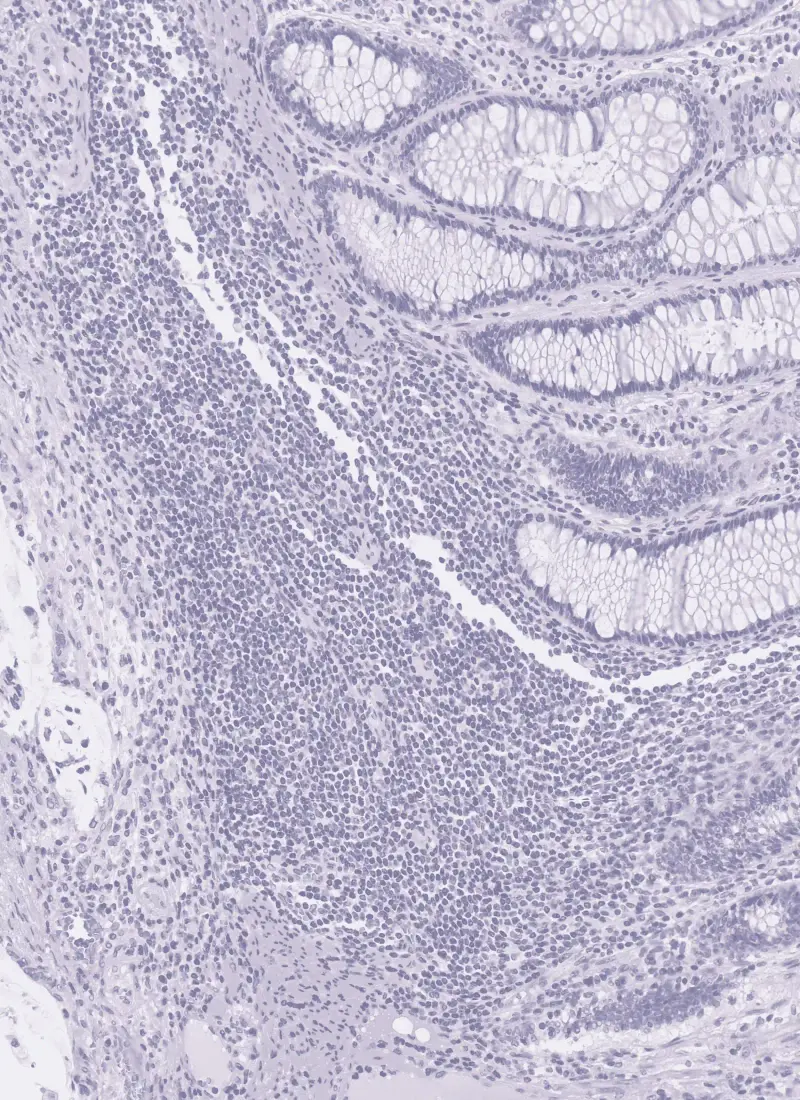

Our AI-powered solution revolutionizes cell detection and classification in digital pathology. By leveraging cutting-edge machine learning algorithms, we can accurately identify and label various cell types within complex tissue samples.

This technology enables pathologists to gain deeper insights into tissue composition, tumor microenvironments, and immune cell infiltration, ultimately leading to more precise diagnoses and personalized treatment strategies.